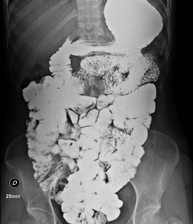

- Double-contrast barium enema

X-ray based diagnostic testing to obtain radiological images of the large intestine (colon and rectum). An opaque contrast agent is administered through the rectum in the form of an enema, and air is also introduced to expand the colon.